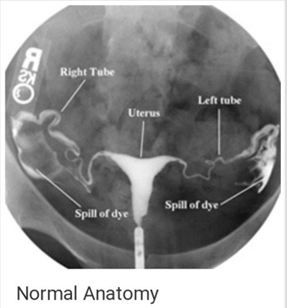

At Pulse Clinic, we are dedicated to providing comprehensive healthcare services that meet the diverse needs of our patients. With a team of highly skilled professionals and cutting-edge technology, we offer a wide range of medical services and diagnostic facilities to ensure your well-being. Here's an overview of the services we provide: